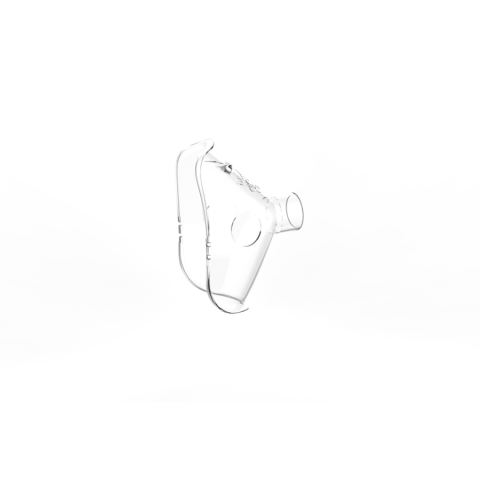

1 kép

1 kép Vivamax Felnőtt maszk GYV17, GYV18 MESH inhalátorokhoz

Felnőtt maszk GYV17, GYV18, GYV29, GYV29V, GYV35 MESH inhalátorhoz

Gyártói cikkszám: GYVMF